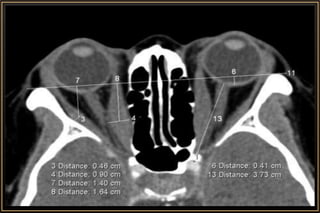

CT ideal for Bony & Traumatic Manifestations

Computed Tomography

Major Considerations

• Slice thickness

• Imaging plane – Axial / Coronal / Sagittal

• Tissue window – Soft or Brain / Bone

• Contrast enhancement – Iohexol (46% Iodine)

• Modification of CT procedure

• #14 Slide Thickness • Spatial resolution of a CT depends on slice thickness. • The thinner the slice, the higher the resolution. • Usually, 2mm cuts are optimal for the eye and orbit. • In special situations (like evaluation of the orbital apex/Optic Nerve), thinner slices of 1mm/1.5mm can be more informative. Modification of CT procedure • Certain cases may require special modifications during the scanning procedure to aid diagnosis. • In a case of orbital venous varix, it is important to request for special scans (with contrast) while the patient performs a Valsalva maneuver. Simultaneous brain CT • Suspected neurocysticercosis with orbital involvement. • Head injury with orbital trauma • Optic nerve meningiomas